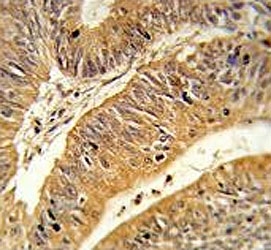

IHC testing of FFPE human colon carcinoma tissue with CXXC4 antibody. HIER: steam section in pH6 citrate buffer for 20 min and allow to cool prior to staining.